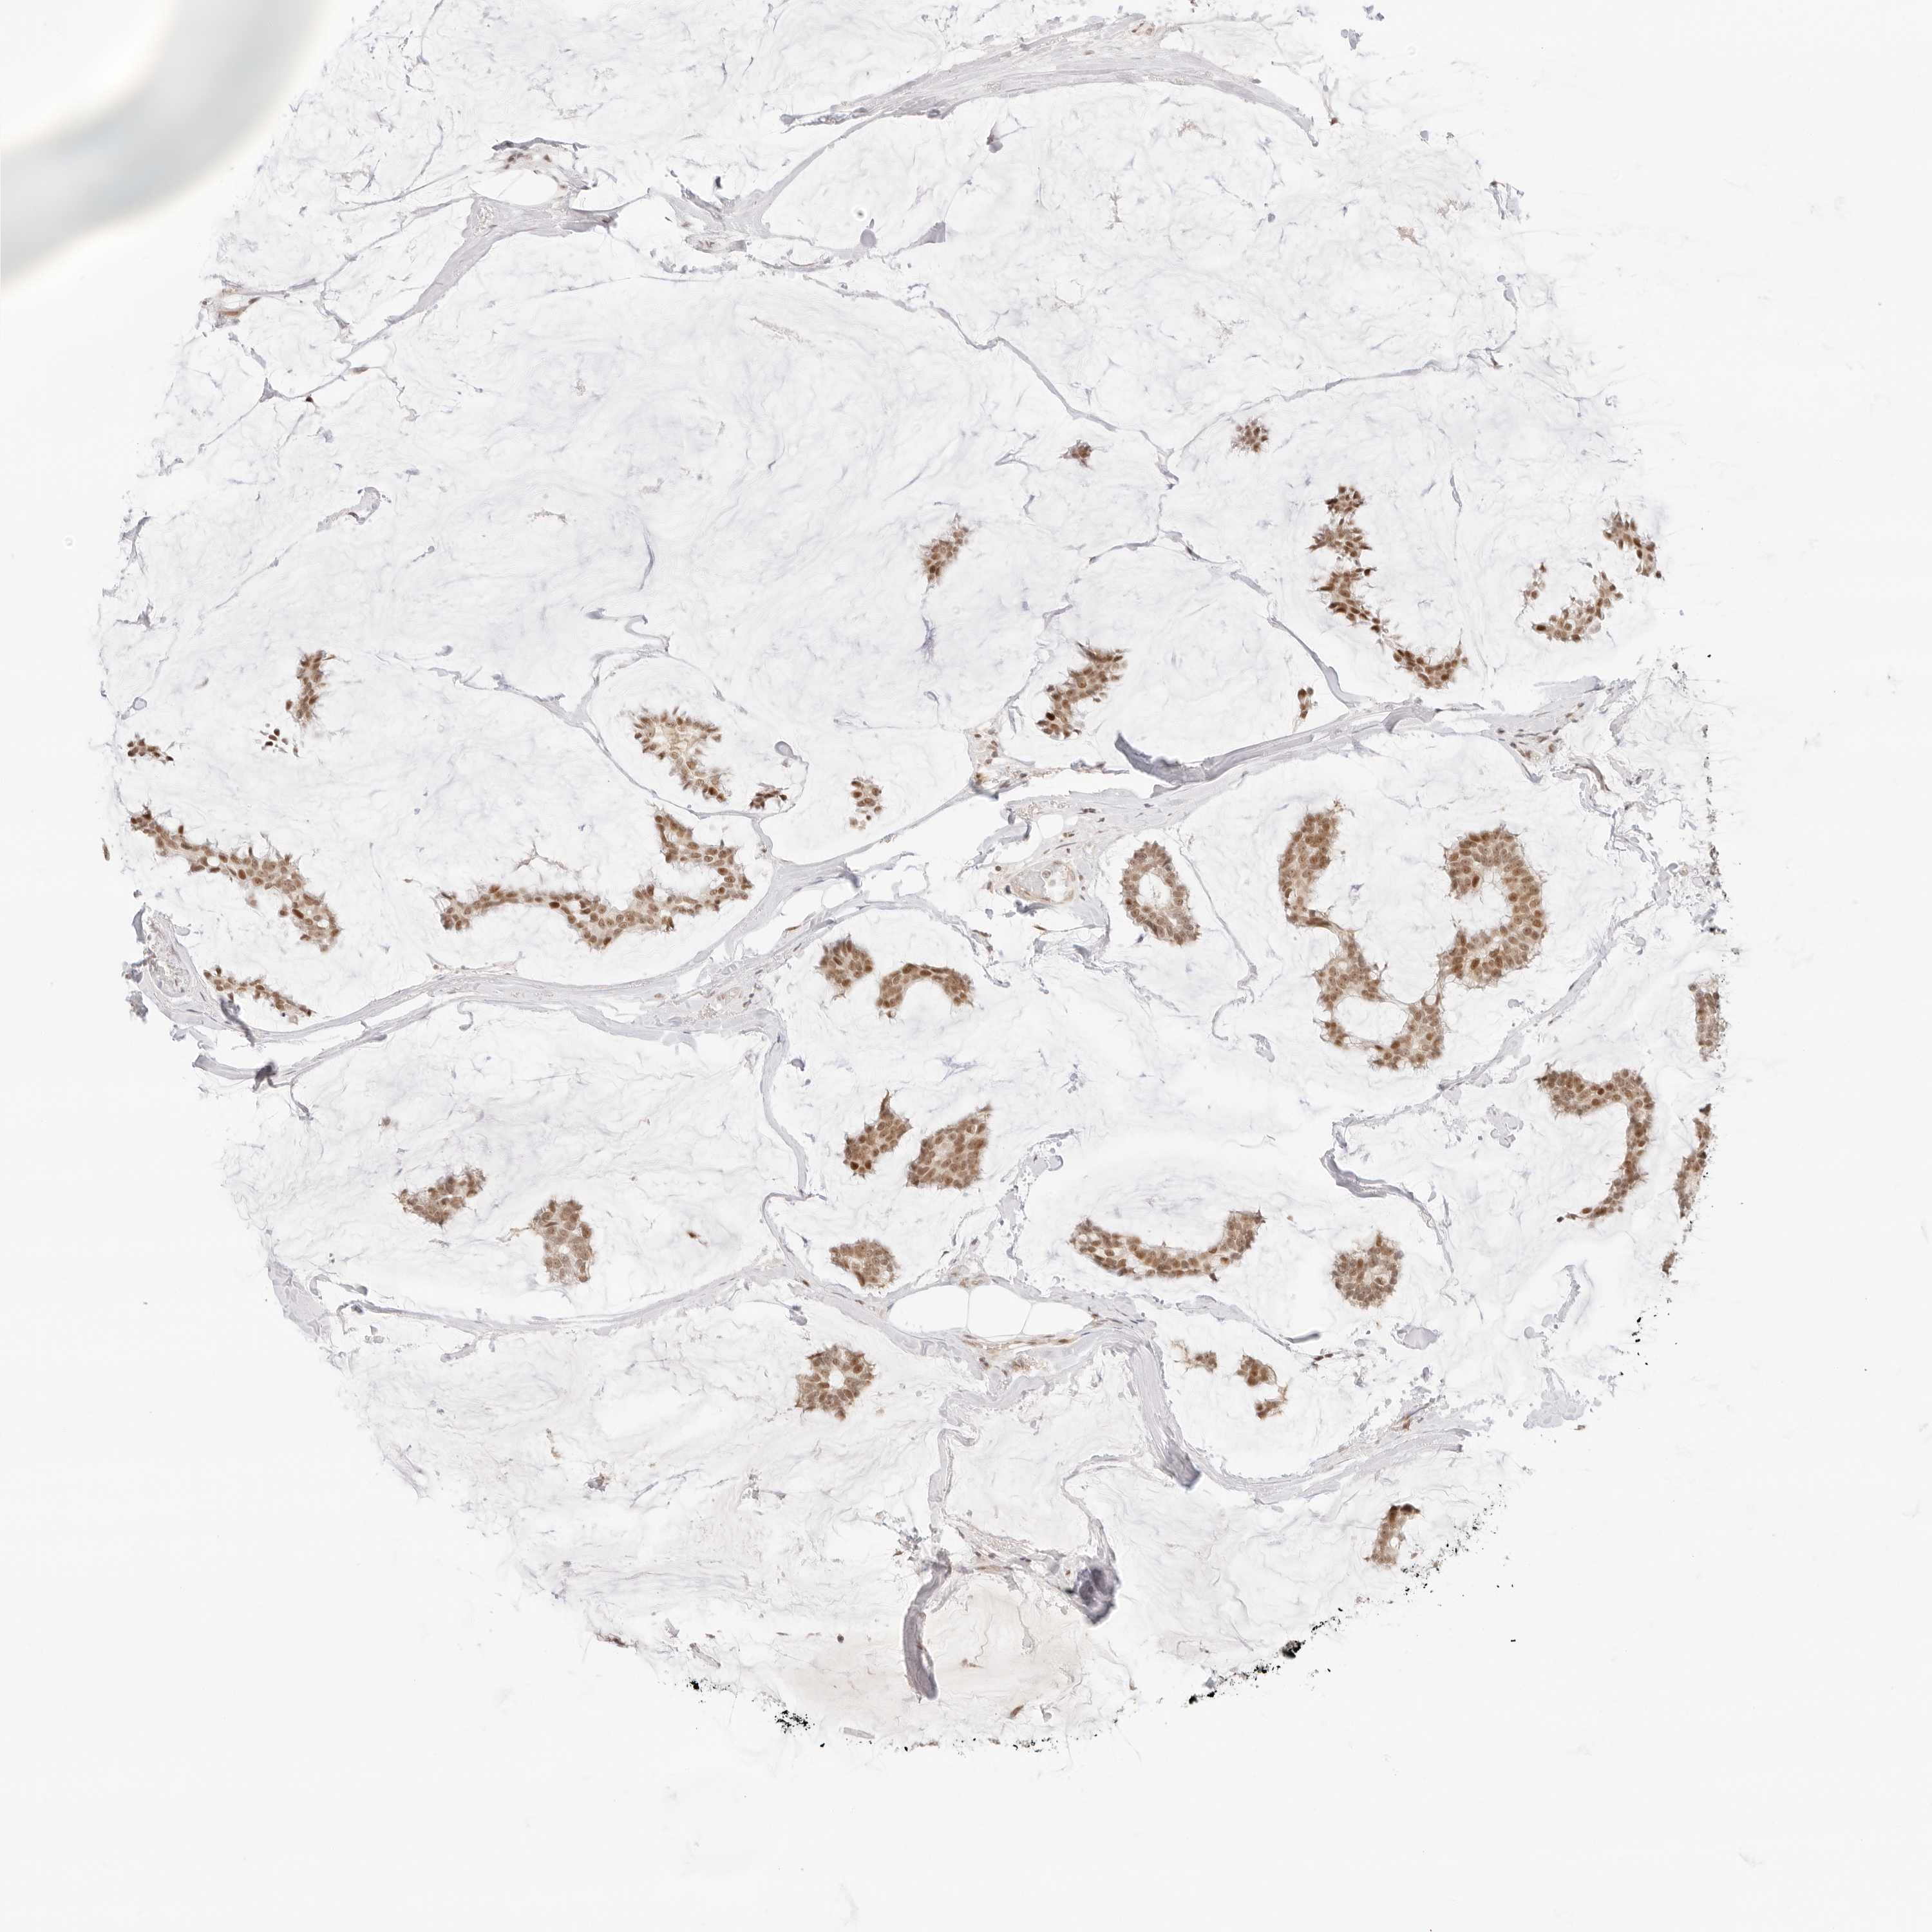

BRCA TCGA BRCA VALIDATION PROTEIN EXPRESSION